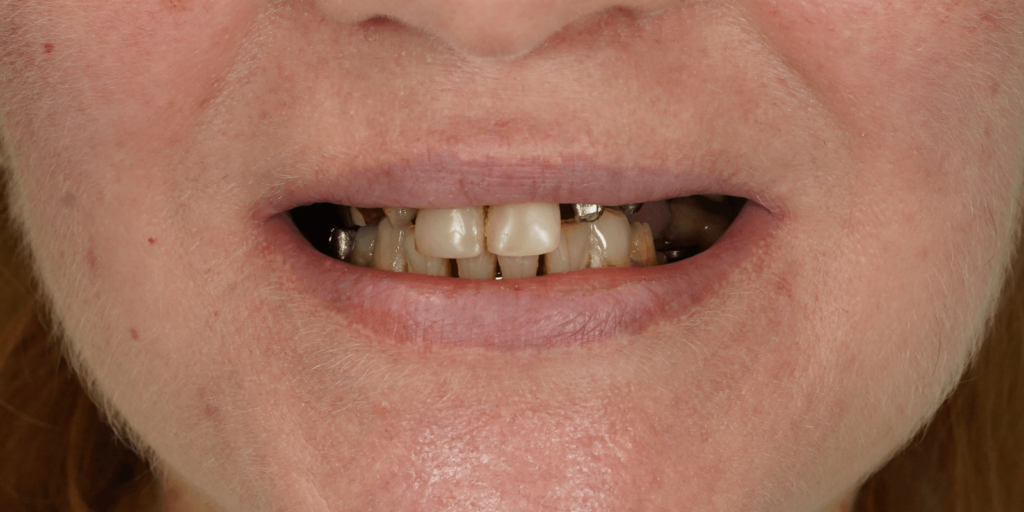

Пациентка обратилась в нашу клинику с жалобами на эстетический дефект зубного ряда, подвижность зубов и на боль в челюсти. Во время осмотра врач выявил:

- На верхней челюсти: 2 мостовидных протеза, 4 отсутствующих зуба, зубную коронку на зубе 2.6, также были обнаружены кариозные полости в двух передних зубах.

- На нижней челюсти: 2 мостовидных протеза и 4 отсутствующих зуба. Зуб 3.8 подвижен, контактирует с антагонистом на верхней челюсти.

Все ортопедические конструкции были из металлокерамики и подлежали замене по нескольким причинам:

- Неудовлетворительное состояние зубов под конструкциями, неудовлетворительный эстетический эффект, изношенность конструкций, необходимость удаления некоторых опорных зубов.